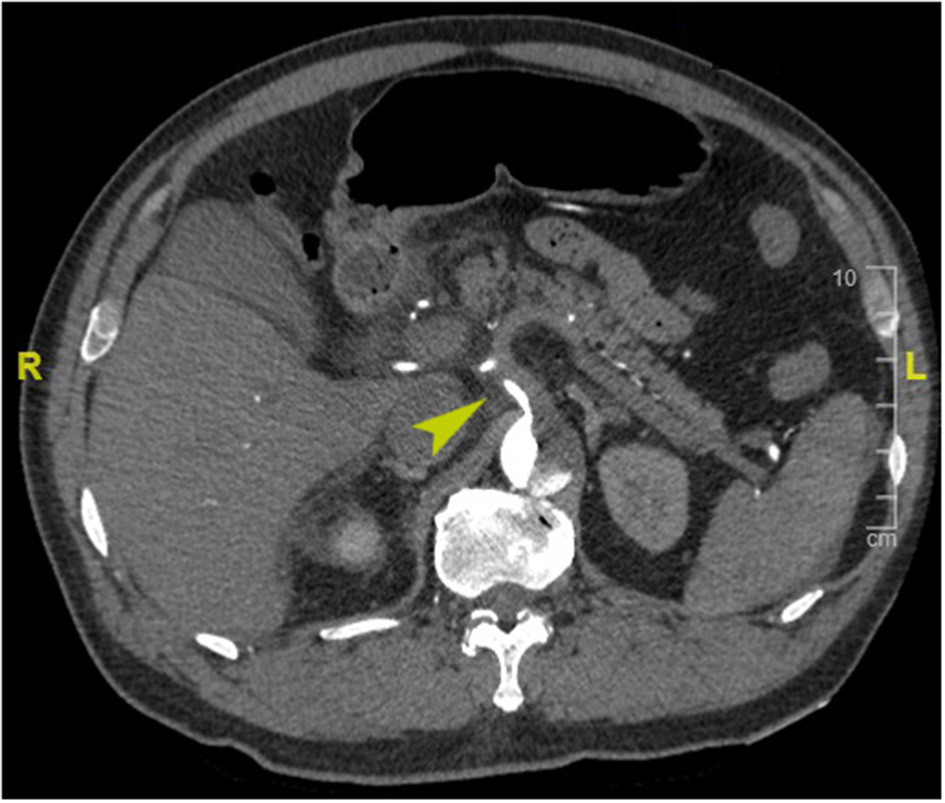

PHD was defined as elevated hepatic transaminase by 1.5 times the upper range of normal within 48 h postoperatively (normal range for aspartate transferase, 0–40 IU/L; for alanine transferase, 0–50 IU/L) according to the International Aortic Arch Surgery Study Group (7). Last available preoperative hepatic transaminase before surgery was used as a baseline value. Death within 30 days of surgery was considered early mortality. Preoperative organ malperfusion was diagnosed based on clinical manifestations and laboratory tests, with CT angiography evidence confirmed (see Appendix E1 for more details). Acute kidney injury was defined as increase serum creatinine ≥1.5 times the baseline or a new requirement for dialysis within 48 h after surgery. We assessed the dissection-related anatomical information including tear extension, branch artery involvement, and branch artery malperfusion based on CT angiography. Dissection involvement referred to vessels that originated from false lumen or combined with intimal tear or malperfusion; branch artery malperfusion was defined as vessels with limited or no flow CT-enhanced signal (Figure 1). Acute dissection was referred to onset within 14 days, and emergency surgery was defined as operation performed within 24 h after hospital arrival. Retrograde perfusion was referred to performing cardiopulmonary bypass (CPB) with cannulation site of the femoral artery, including double arterial cannulation (8). We collated clinical data retrospectively from laboratory reports, radiological examination reports, and medical charts, follow-up data were obtained by telephone interview or clinic visits.

Figure 1

Enhanced computed tomography angiography image of a representative case of preoperative celiac trunk malperfusion (arrowhead).